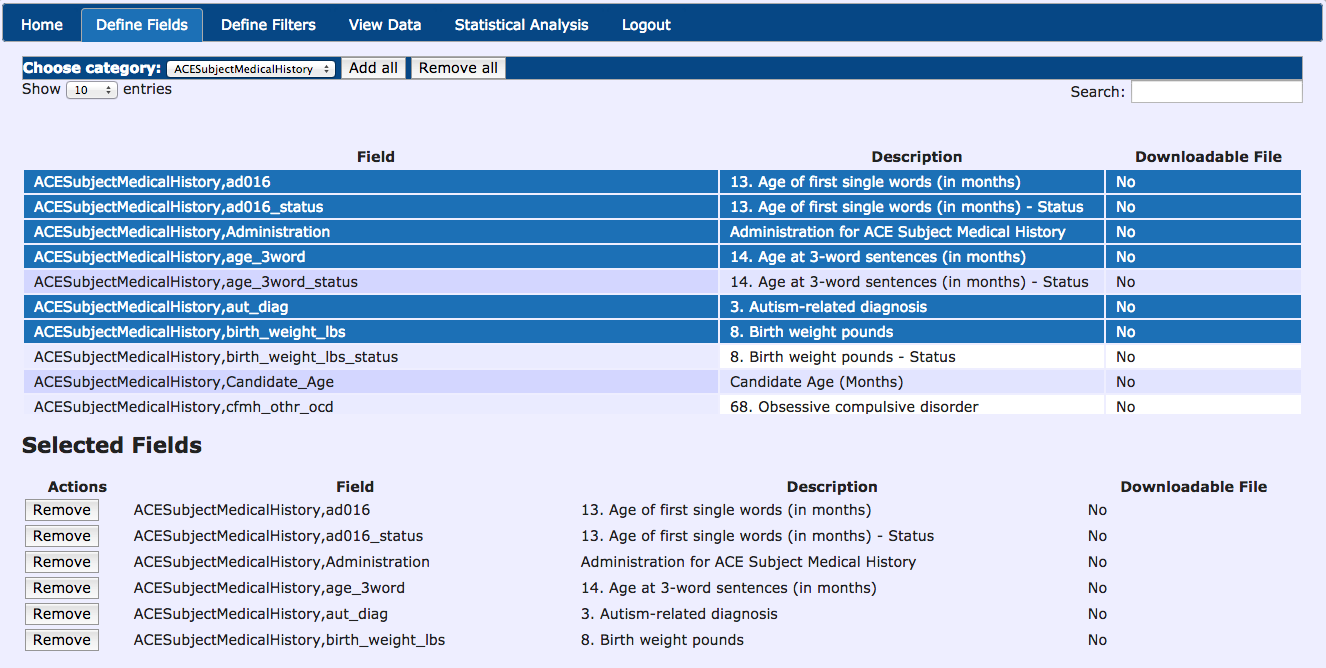

Data Querying Tool

- Multimodal Data Querying - Easy querying of data, without requiring a programmer